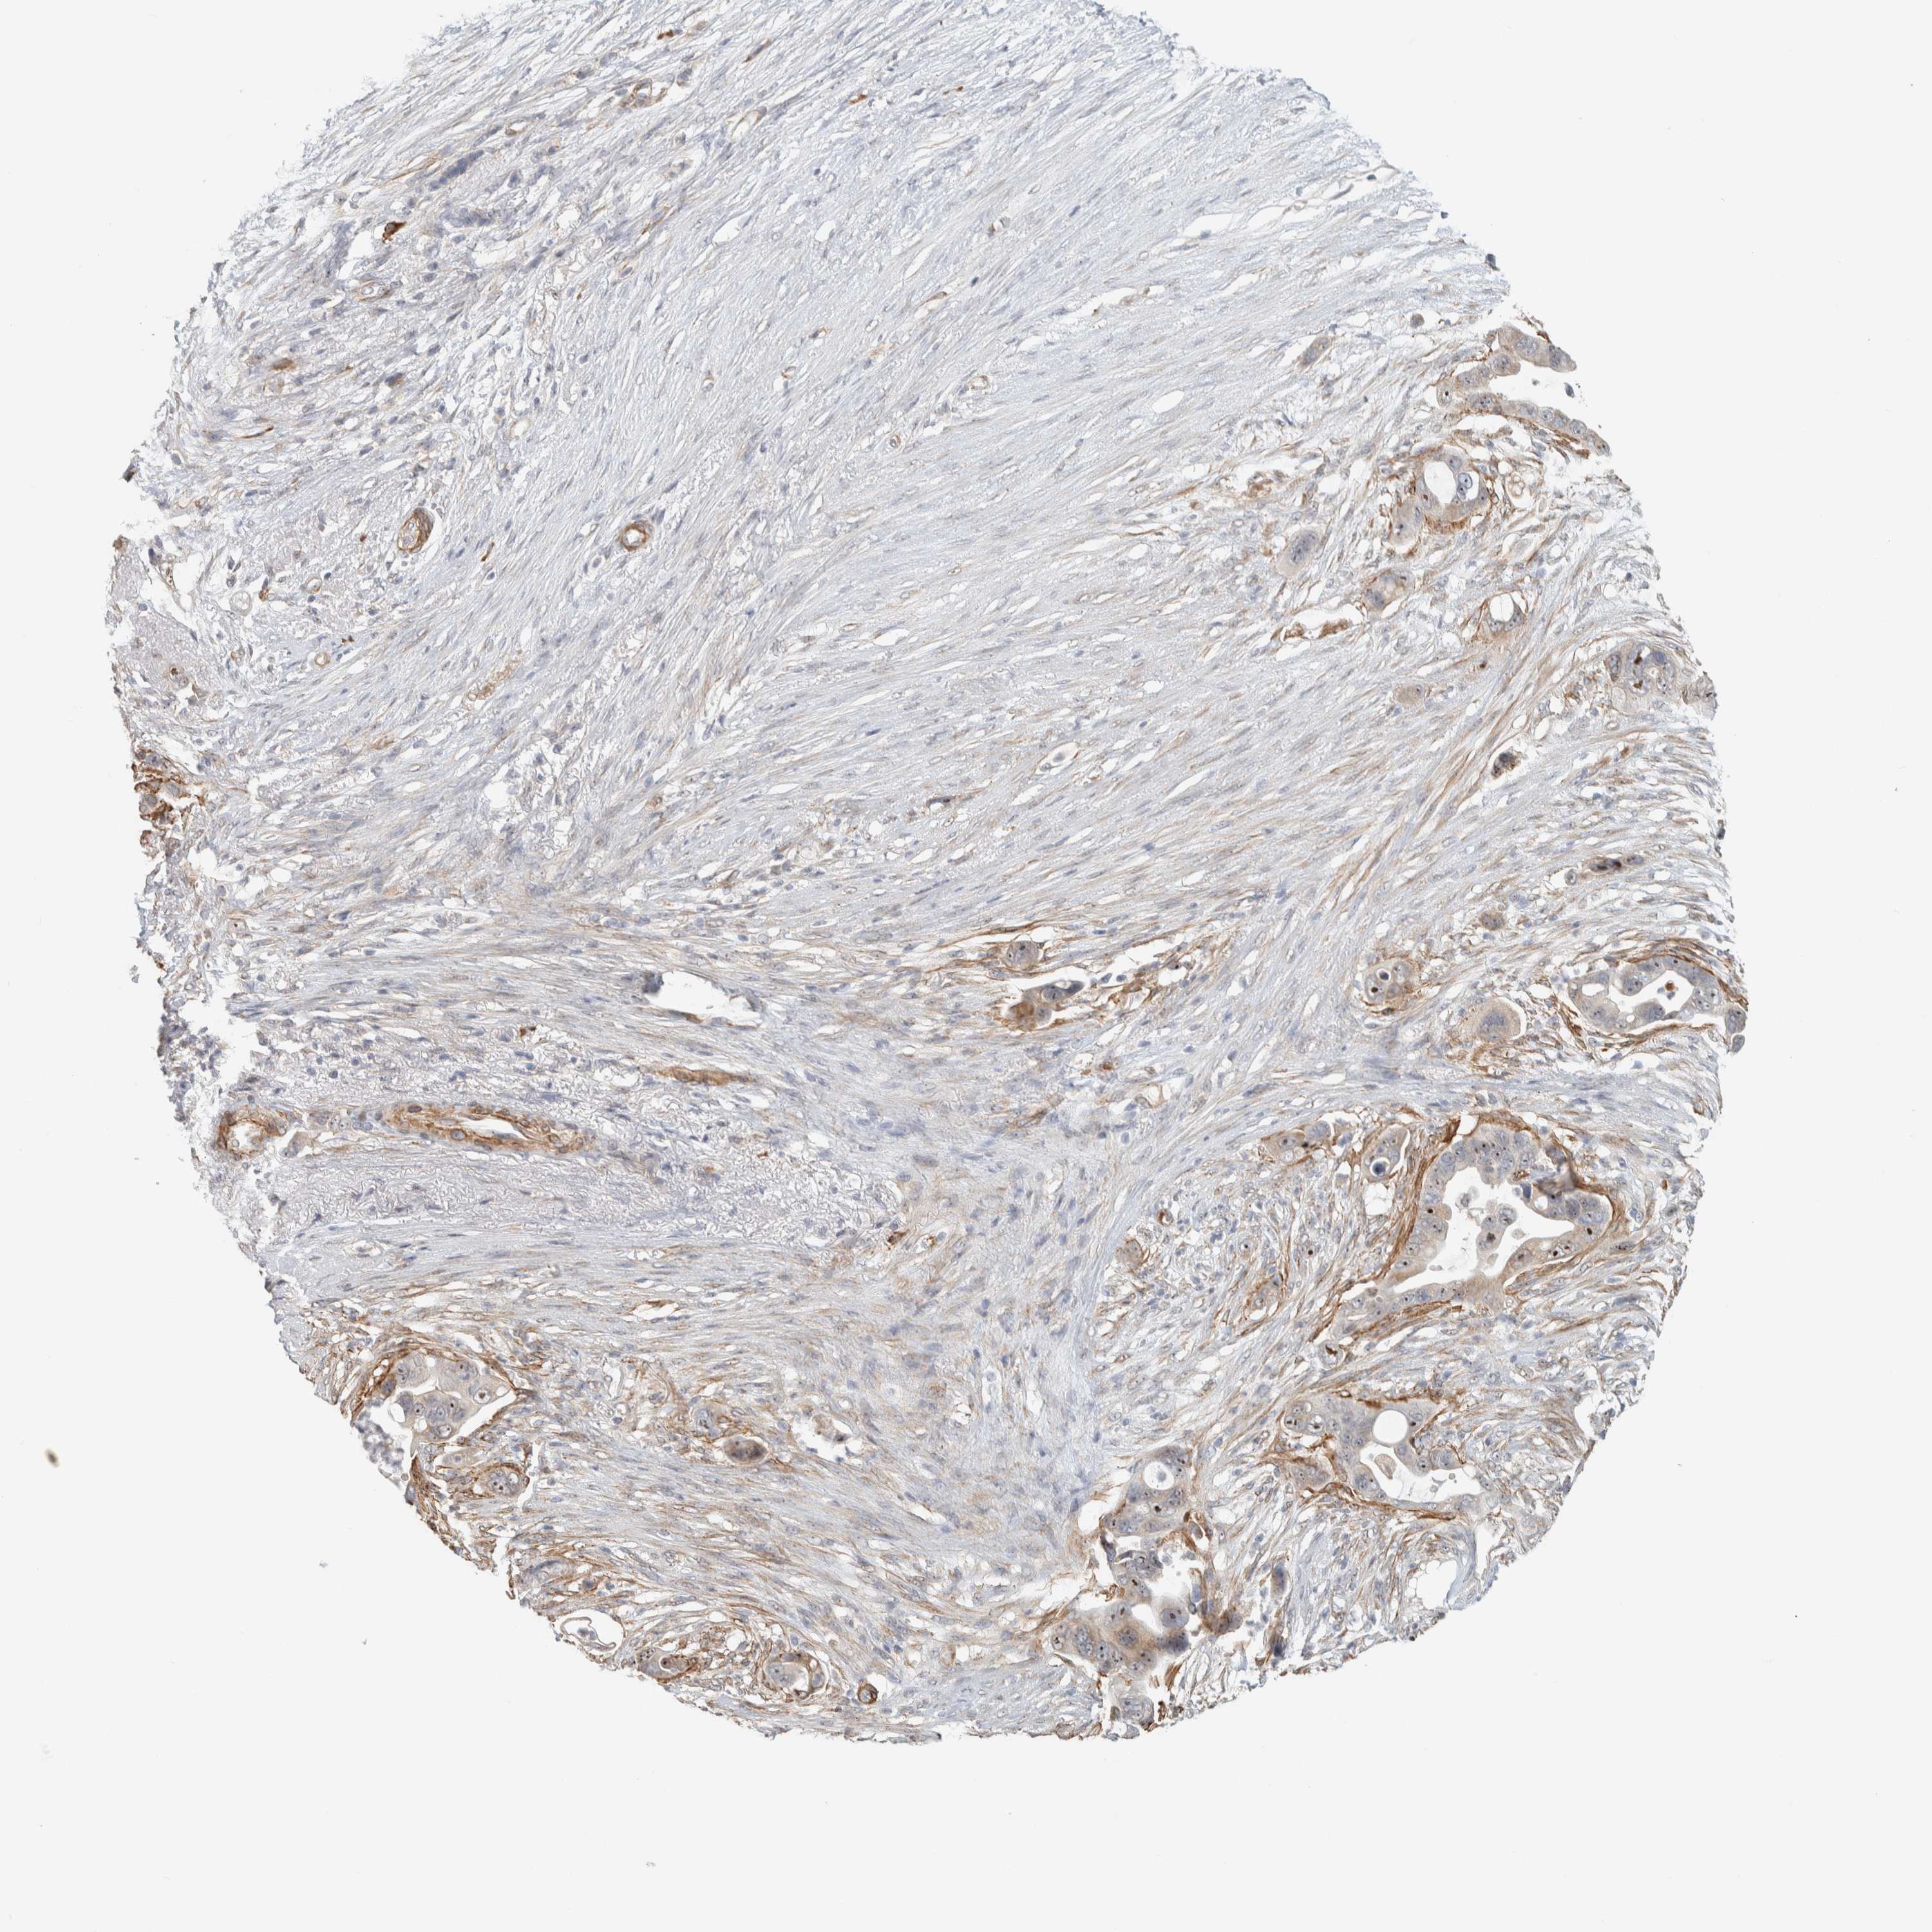

PANCREATIC CANCER - Protein expressioni

A mouse-over function shows sample information and annotation data. Click on an image to view it in a full screen mode. Samples can be filtered based on level of antibody staining by selecting one or several of the following categories: high, medium, low and not detected. The assay and annotation is described here.

Note that samples used for immunohistochemistry by the Human Protein Atlas do not correspond to samples in the TCGA dataset.

Antibody stainingi

Antibody staining in the annotated cell types in the current human tissue is reported as not detected, low, medium, or high, based on conventional immunohistochemistry profiling in selected tissues. This score is based on the combination of the staining intensity and fraction of stained cells.

Each image is clickable and will lead to virtual microscopy that enables deeper exploration of all samples and also displays staining intensity scores, fraction scores and subcellular localization as well as patient and tissue information for each sample.

Antibody HPA024463

Antibody HPA052201

Staining

High

Medium

Low

Not detected

Intensity

Strong

Moderate

Weak

Negative

Quantity

>75%

75%-25%

<25%

None

Location

Nuclear

Cytoplasmic/membranous

Cytoplasmic/membranous,nuclear

Adenocarcinoma, NOS